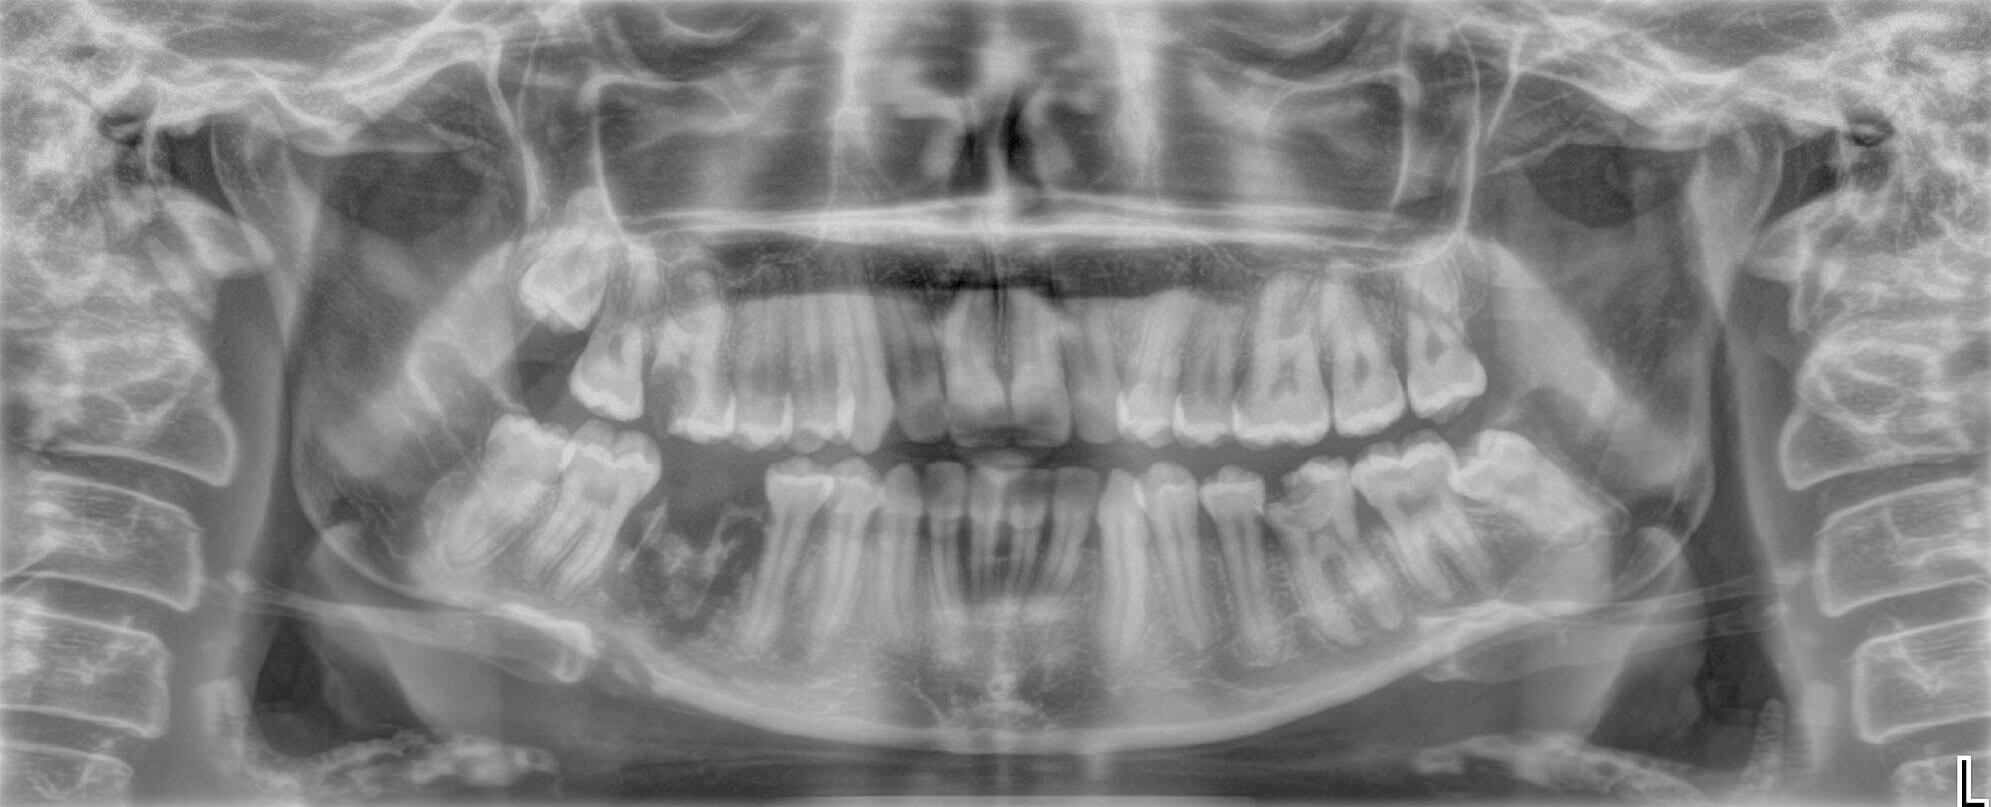

Figure 3: OPG showing extent of osteomyelitis at presentation to OMFS department.

An Orthopantomagram (OPG) demonstrated a pathological fracture through extensive OM area around the right body of the mandible with proliferative periostitis indicating chronicity (Figure 3). A cone-beam CT scan confirmed this fracture.

A working diagnosis of a pathological right body mandibular fracture due to osteomyelitis following a dental extraction was made. This was then further subclassified as secondary chronic OM.